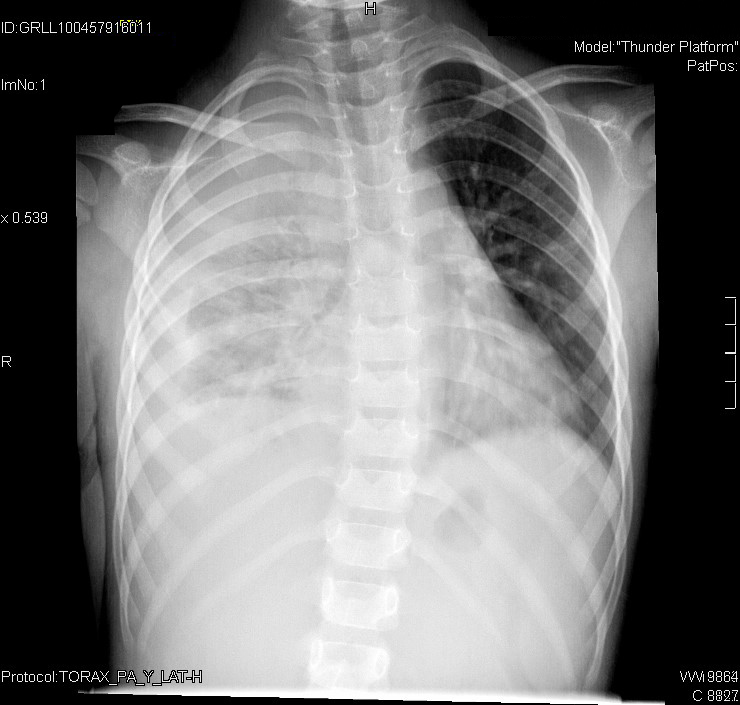

Tras 48 horas con tratamiento antibiótico, persiste la fiebre y aparece un dolor súbito en el costado derecho, por lo que se realiza una radiografía de tórax de control.

Ante el hallazgo de derrame pleural, solicitamos una ecografía torácica, que es informada como: marcado derrame pleural derecho y hepatización del pulmón adyacente, con zona máxima de grosor del derrame de 19 mm.